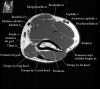

2. Axial section

1) The tendons of the Biceps Brachii and Brachiallis muscles transversely as they insert onto the Radius and Ulna respectively. 2) The distal Triceps tendon is also well evlauated in this plane.